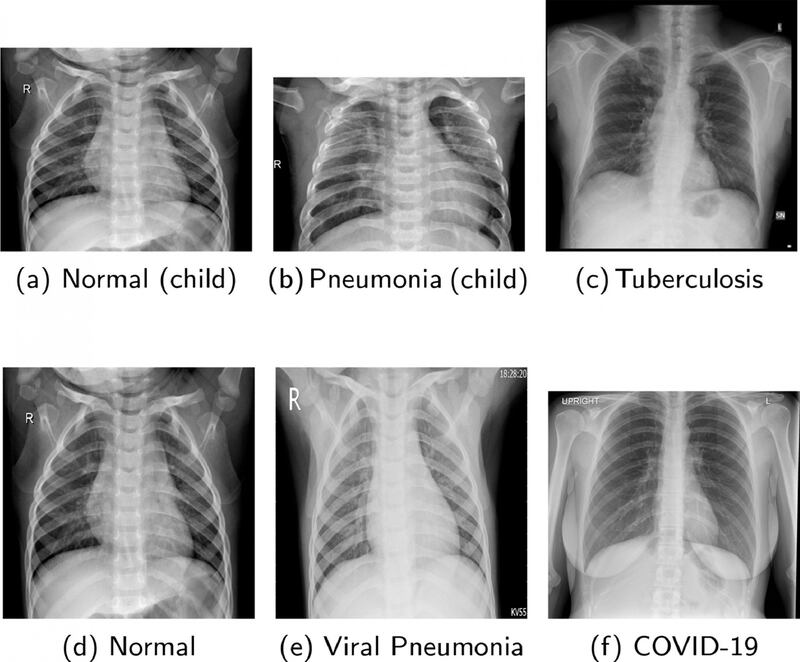

El equipo creado por la UWS usa imágenes de rayos X, comparándola con una base de datos de miles de imágenes de pacientes con neumonía, tuberculosis y COVID-19.

En este caso, el entrenamiento consiste en que el software analice miles de imágenes de radiografías de pacientes.

Mediante la red neuronal convolucional profunda, se comparan imágenes, determinando la existencia o no de alguna enfermedad.